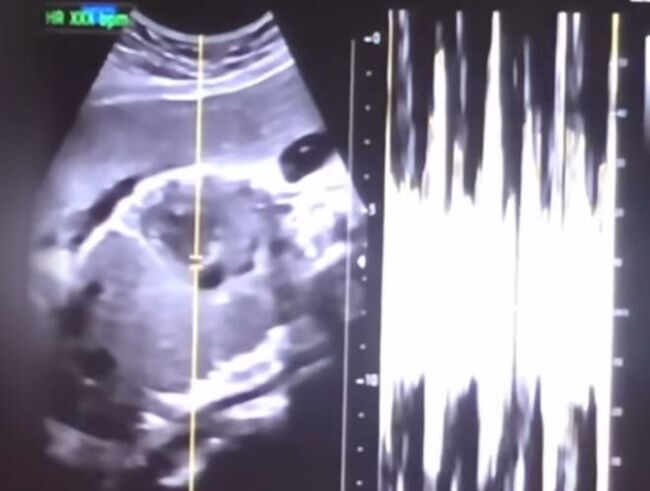

▲ 낙태한 산모의 유튜브 동영상에서 캡쳐한 초음파 사진과 심박 그래프 (사진=서울중앙지검 제공)

윤씨는 권씨가 유튜브에 임신 36주 차에 낙태한 경험담을 유튜브에 올려 논란이 되자 지난해 7월 12일 사산 증명서를 허위로 발급했고, 증명서는 화장대행업자 등에게 건네진 것으로 검찰은 파악했다.

이번 사건은 권씨가 유튜브에 올린 낙태 관련 영상을 두고 살인이 아니냐는 논란이 불거지자 보건복지부가 지난해 7월 경찰에 진정서를 내면서 수사가 시작됐다.